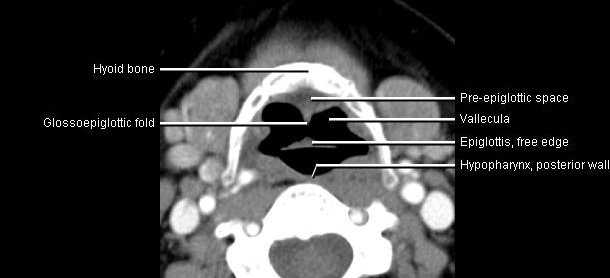

Phonation and dysphagia involve multiple coordinated structures in the larynx and pharynx. Radiation induced dysphagis appears to be related to dose to the phyaryngeal constrictor muscles and specific regions of the supraglottic and glottin larynyx.

Speech is impacted by doses to the epiglottis, base of tongue, aryepiglottic folds, false vocal cords upper esophageal sphincter and cricoid cartilage.

The mean laryngeal volume receiving > 50 Gy was a predictor of laryngeal edema. Vocal functions are usually well preserved with doses of 60 - 66 Gy. Dornfeld found a strong correlation between speech quality and dose to the ariepiglottic folds, pre-epiglottic space, false vocal cords and lateral pharyngeal walls at the level of the false vocal cords. A steep decrease in dose function was noted when doses exceeded 66 Gy.